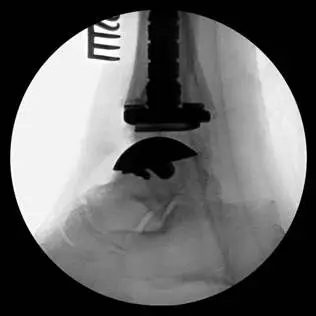

This is a pic of the implant getting mapped out for placement in the distal tibia

This is the guide for the tibia component of the implant